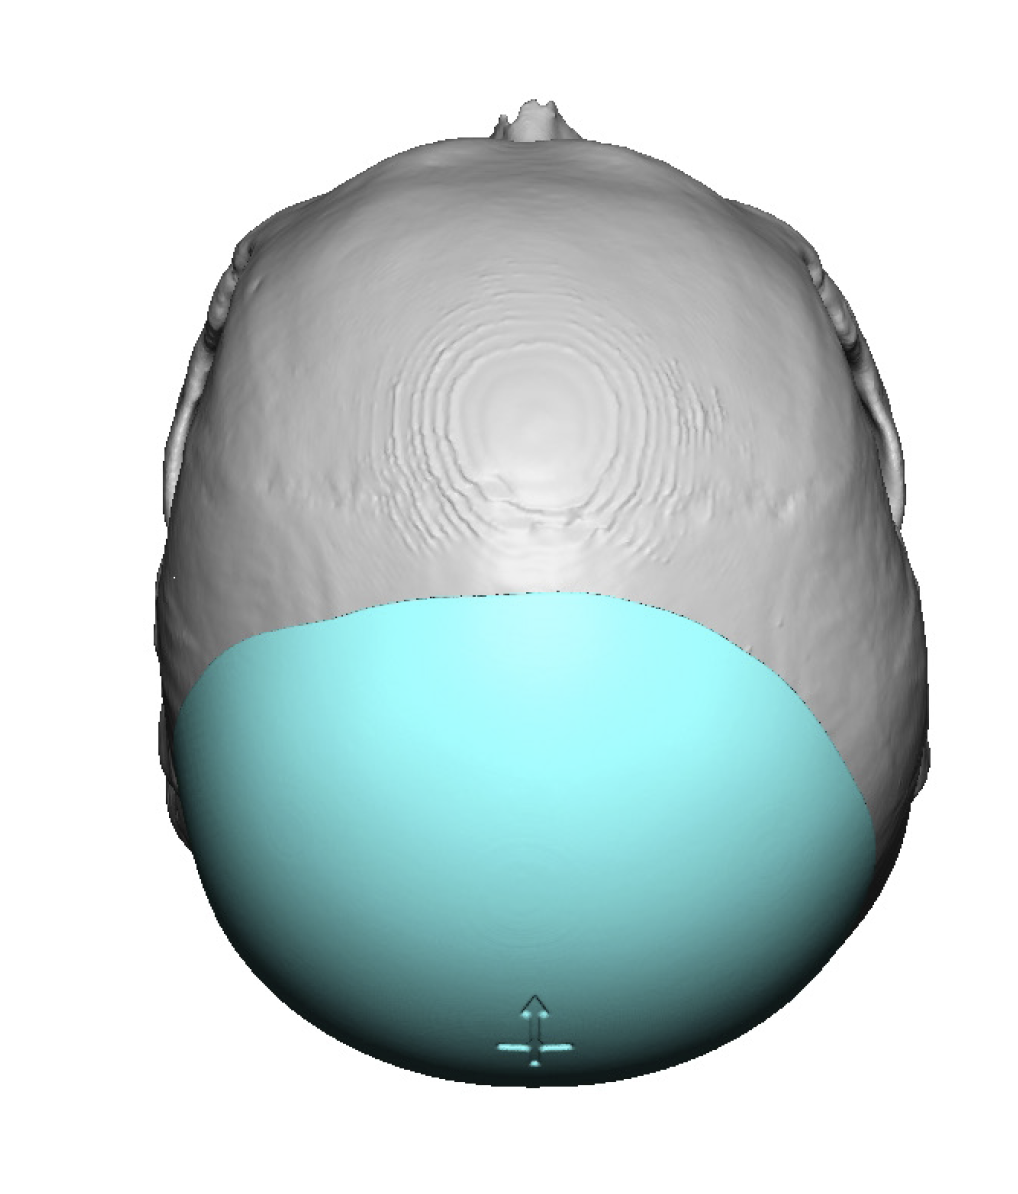

Patient 11

Desire to build out the back of his head which had bothered him his whole life.

Two-stage skull augmentation of the back of the head using a custom skull implant as the second stage. (first stage scalp expansion)

Desire to build out the back of his head which had bothered him his whole life.

Two-stage skull augmentation of the back of the head using a custom skull implant as the second stage. (first stage scalp expansion)